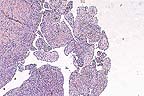

Florid biliary proliferation within portal areas and multifocal aggreates of medium numbers of lymphocytes in a cat with lymphocytic cholangiohepatitis. (HE, 100X, 83K)

Contributor's Diagnosis and Comments: Liver: Cholangiohepatitis, lymphoplasmacytic, chronic, periportal, diffuse and bridging, with nodular hyperplasia and marked bile duct proliferation, Domestic Shorthair cat, feline.

Feline cholangitis/cholangiohepatitis syndrome occurs in three histologic forms: suppurative cholangitis/cholangiohepatitis, long-term nonsuppurative cholangitis/cholangiohepatitis, and biliary cirrhosis. The three forms are thought to be progressive stages of the same disease. Initial inflammation of the biliary system spreads to the adjacent hepatic parenchyma. The long-term result is portal fibrosis and biliary hyperplasia. The etiology of the disease is unknown, although immune-mediated mechanisms have been proposed. Additionally, bacterial and parasitic infections (including toxoplasmosis) have been associated with suppurative cholangitis. Many cats with the disease respond favorably to corticosteroid and/or antibiotic therapy. Biochemical findings vary. Aspartate aminotransferase, alanine aminotransferase, and alkaline phosphatase enzymes are often high in the suppurative form, but can become normal as the disease progresses. Hyperbilirubinemia is common. In the present case, a causal relationship was not established between the toxoplasmosis and liver lesions.

AFIP Diagnosis: Liver: Biliary hyperplasia and fibrosis, bridging, diffuse, marked, with hepatocellular loss, nodular regeneration, and lymphoplasmacytic and neutrophilic cholangiohepatitis, Domestic Shorthair, feline.

Conference Note: Although the three histologic forms of feline cholangiohepatitis syndrome (suppurative, non-suppurative, and biliary cirrhosis) may represent a progression of lesions of the same cause, there are some inconsistancies with this theory. For example, while it might be assumed that the nonsuppurative form is a more chronic stage of the suppurative form, the nonsuppurative lesion seems to occur in a generally younger group of cats than the suppurative form.

Suppurative cholangitis/cholangiohepatitis is characterized by portal and parenchymal infiltration of neutrophils, accompanied by mild fibrosis and bile duct hyperplasia. Suppurative cholangiohepatitis is most common in middle-aged to old cats. Enteric bacteria are frequently isolated from these lesions and ascending bacterial infection of the bile duct has been proposed as the etiology; however, cholelithiasis, trematodes, the nephrotic syndrome, and protozoa have also been associated with suppurative cholangiohepatitis.

Nonsuppurative cholangiohepatitis is characterized by portal infiltrates of plasma cells and lymphocytes, bile duct hyperplasia, and periportal fibrosis; small numbers of neutrophils may be present. Nonsuppurative cholangiohepatitis has also been associated with pancreatitis. Cats less than 4 years of age are primarily affected.

Biliary cirrhosis is presumed to result from progressive cholangiohepatitis; however, the etiology is unknown. Histologically, there is prominent bridging portal fibrosis, bile duct hyperplasia, nodular hyperplasia, and chronic inflammation of varying severity. Regardless of etiology, the prognosis for any form of cholangiohepatitis is guarded due to a generally poor response to therapy.

Some attending the conference diagnosed cholangiocarcinoma; however, there are several features that argue against a neoplastic process. At the center of most of the areas of bile duct hyperplasia, there are pre-existent portal structures, suggesting a diffuse proliferative lesion rather than widespread portal invasion of neoplastic cells. Additionally, there is little cellular atypia of the proliferating epithelial cells, the proliferating ducts are linedby a single layer of cells, and the mitotic rate is low. Also, nodular hepatocellular regeneration and biliary hyperplasia are not commonly associated with cholangiocarcinoma.